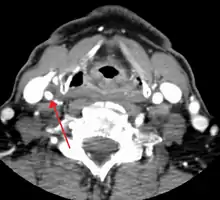

One of several different imaging modalities, such as a computed tomography angiogram (CTA)[18][19][20] or magnetic resonance angiogram (MRA) may be useful. Each imaging modality has its advantages and disadvantages - Magnetic resonance angiography and CT angiography with contrast is contraindicated in patients with chronic kidney disease, catheter angiography has a 0.5% to 1.0% risk of stroke, MI, arterial injury or retroperitoneal bleeding. The investigation chosen will depend on the clinical question and the imaging expertise, experience and equipment available.[21]